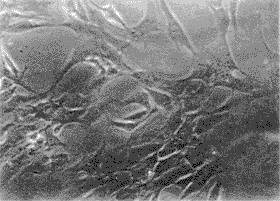

人OB形状主要为三角形和四方形,5 d左右长满瓶底,此时细胞外观为铺路石状(图1)。用钙-钴法进行ALP染色,大部分细胞为阳性,胞浆染成棕黑色。

图1 第二代人成骨细胞(倒置显微镜,×100)